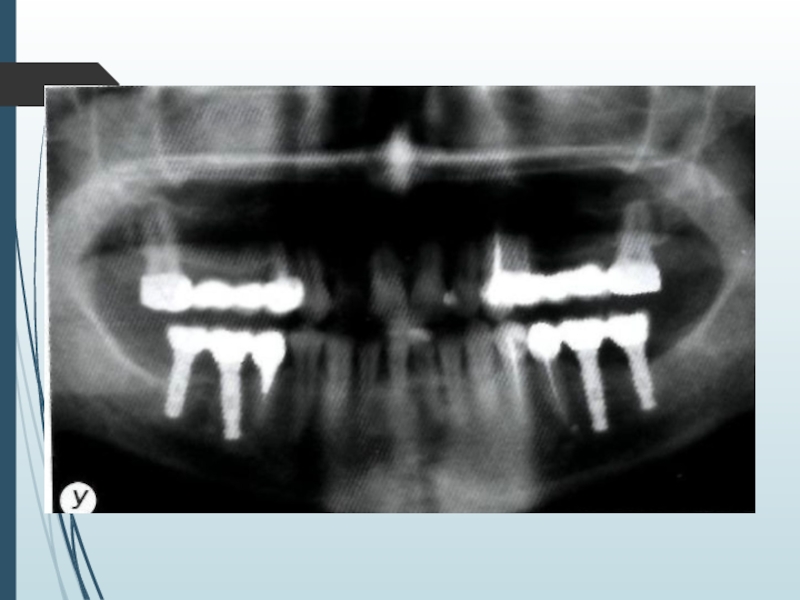

Слайд 13Компьютерная томография является одним

из наиболее информативных методов рентге-

нологического

обследования. С высокой степенью достоверности она

позволяет определить высоту и

ширину кости,

топографию нижнечелюстных каналов и верх-

нечелюстных пазух, особенности архитектони-

ки различных отделов челюстей, соотношение

последних, а также создать трёхмерное изоб-

ражение лицевого отдела черепа

Компьютерная томография является одним из наиболее информативных методов рентге- нологического обследования. С высокой степенью достоверности она позволяет